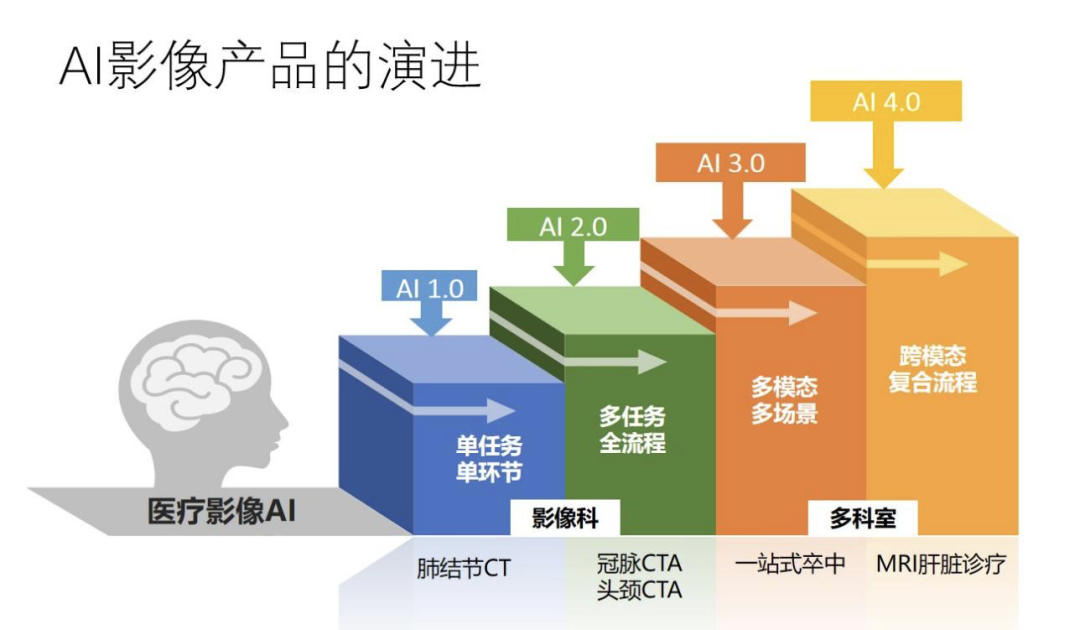

下面我从产品本身如何去迭代和演化的角度做一个简要的介绍。从 2015 年开始,产品从复杂程度、算法和产品设计的过程来看,大概经历了四个阶段,我们称之为 1.0-4.0,从最初 2015 年的单任务单环节,过渡到多任务全流程,再过渡到多模态多场景,到现在的跨模态复合流程。从仅限影像科,到现在进入临床手术,经历了比较大的变化。

在 1.0 阶段,大家都扎堆做肺结节影像,这个任务相对来说比较简单,在 CT 图像上进行结节的检测、分割以及良恶性的分类,只需要有一些数据和基本的深度学习、图像的算法经验就可以做起来,门槛低,同质化竞争严重。同时产品的市场竞争力和盈利能力也是比较低的。

到了 2018、2019 年,AI 影像的产品开始从单任务、单环节拓展到多任务、全流程的场景,我们称之为 2.0 阶段。其中一个比较有代表性的产品就是数坤科技做的冠脉和头颈 CTA,涉及到多个算法任务串联起来的流程,只有这个流程全部自动化之后,才可以为医生提供比较大的价值,解决医疗行业的痛点。如图所示,传统流程可能需要花 60 分钟才能完成这些步骤,而在 AI 流程下,很多环节被自动化的算法取代,因此只需花费 10 分钟,效率大大提高,这就是 2.0 产品带给医疗场景的价值。

到了 3.0 阶段,我们就不仅需要处理单一的场景单一的流程,而是过渡到一个更加复杂的诊断和治疗任务。以脑卒中为例,我们要判断病人是不是脑缺血,第一步首先要做 CT 的平扫,通过 ASPECT 评分大概查看大脑内部有哪个区域可能缺血,当我们知道确实有一些区域有缺血症状之后。下一步需要找到哪一根血管发生堵塞导致缺血,因此要做一个脑部 CTA 来寻找原因。定位原因之后,下一步要确定治疗方案,是打开血管进行手术,还是做保守治疗,因此第三步是做一个更加复杂的脑部 CTP,在一个时间序列内关注脑部所有区域缺血的严重程度,最右边的图中绿色区域就表示比较健康的供血正常区域,红色就表示缺血区域。如果缺血的程度不是很严重,就有可能采取一个比较激进的治疗方案,比如做手术取栓。如果缺血比较严重,那么做手术就可能有危险,因此会采取一个相对保守的治疗方案。可见,对于这样一个比较复杂的病种需要做三个不同阶段的扫描,多模态数据分析和判断过程是串联起来的,每一个模块都有各自的作用。

到了 4.0 阶段,除了需要处理多模态数据之外,多模态数据之间的关系也不再是串联和各司其职的简单关系,而是它们之间互相有关联、互为因果。以核磁肝脏诊疗为例,每一个 case 会拍多达十几个序列,每一个序列是不同核磁的征象,AI 产品需要在不同的序列上找到病灶征象,并做出综合的判断和分析,不同序列之间的数据是要统合考虑的。医生做出判断和分析的整个过程是比较复杂的,因此必须要复杂程度 4.0 的产品才可以很好地实现自动化。这是我简要介绍了一下从 2015 年开始到现在的发展历程。